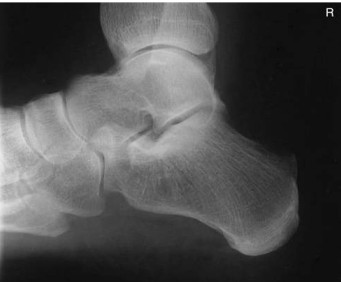

1 inch (2.5 cm) inferior to medial malleolus

Should the foot be dorsiflexed or left in a neutral position for this mediolateral calcaneus projection?

Dorsiflex foot

What anatomy is correctly demonstrated on this lateral calcaneus

calcaneus demonstrated in profile with talus and distal tibfib demonstrated superior and navicular and open joint space of the calcaneus and cuboid demonstrated distally

On this lateral calcaneus image, what indicates no rotation?

superimposed superior parts of the talus, open talocalcaneal joint, lateral malleolus superimposed over posterior half of the tibia and talus. Tarsal sinus and calcaneocuboid joint space should appear open